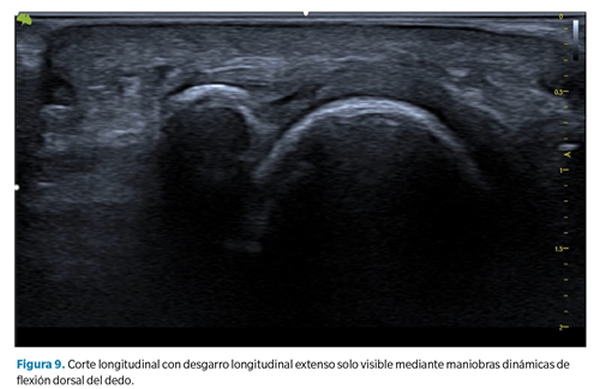

2. Aplanamiento y atenuación de la placa plantar. En estos casos no se observa un defecto de forma tan clara, pero debe llamarnos la atención cuando la zona de inserción, generalmente más gruesa, se aprecia más adelgazada que la zona media o proximal de la placa. Esto sugiere generalmente la presencia de un desgarro transversal que abarca desde la porción lateral hasta la porción central de la placa40 (Figura 9).

Como se ha señalado, en todos los casos las maniobras dinámicas de tensión del dedo (y la placa) son esenciales para establecer la presencia o no de un desgarro y su magnitud41,42. La incapacidad de tensar la placa (pasar de su estado curvado a un estado lineal) así como la pérdida de movimiento congruente entre la falange proximal y la placa son signos muy sugerentes de desgarro que solo pueden apreciarse mediante dichas maniobras.